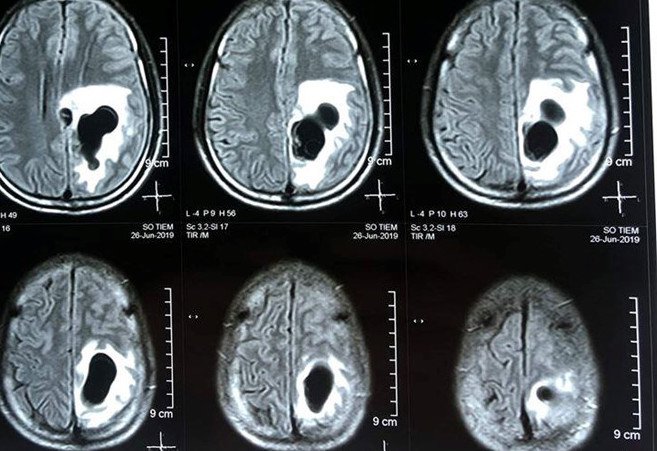

- Cộng hưởng từ (MRI) sọ Não tiêm thuốc đối quang là phương pháp dùng thuốc đối quang (contrast media) đưa vào cơ thể nhằm tăng sự tương phản của các cấu trúc giải phẫu mà bình thường khó thấy được hoặc khó phân biệt được với các cấu trúc xung quanh, sau đó sử dụng từ trường và sóng vô tuyến để tạo ra hình ảnh cắt ngang rõ ràng và chi tiết và rõ nét về sọ não, nhất là U não do vậy giúp đánh giá và phát hiện những tổn thương, bất thường của sọ não từ rất sớm.

Bước 5. Xử lý hình ảnh, sau đó bác sĩ đọc tổn thương, mô Tả trên máy tính kết luận và in kết quả. Hình ảnh hiển thị phải đảm bảo hiển thị được rõ các cấu trúc giải phẫu trong vùng thăm khám, phát hiện được tổn thương, đánh giá tính chất ngấm thuốc.